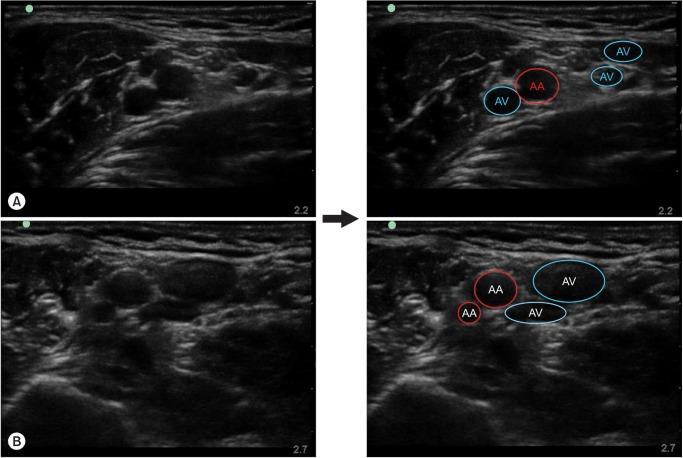

One hundred and thirty-one patients scheduled to undergo surgery in the region below the elbow were enrolled after giving their informed written consent. Using the 5-12 MHz linear probe of an ultrasound system, we examined cross-sectional images of the brachial plexus in the supine position with the arm abducted by 90°, the shoulder externally rotated, and the forearm flexed by 90° at the axillary fossa. The results of the nerve positions were expressed on a 12-section pie chart and the numbers of arteries and veins were reported.

Applying gentle pressure to prevent vein collapse, the positions of the nerves changed easily and showed a clockwise order around the axillary artery (AA). The most frequent positions were observed in the 10-11 section (79.2%) for the median, 1-2 section (79.3%) for the ulnar, 3-5 section (78.4%) for the radial, and 8-9 section (86.9%) for the musculocutaneous nerve. We also noted anatomical variations consisting of double arteries (9.2%) and multiple axillary veins (87%).

Using real-time ultrasonography, we found that the anatomical pattern of the major nerves in Koreans was about 80% of the frequent position of individual nerves, 90.8% of the single AA, and 87% of multiple veins around the AA.